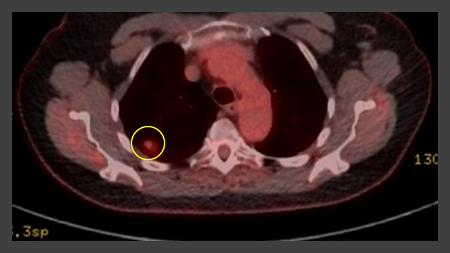

PET-CT com 18-fluordesoxiglucose (18-FDG) mostrando lesão periférica de alta captação no pulmão esquerdo. A ressecção cirúrgica confirmou câncer pulmonar de células escamosas moderadamente diferenciado

Do acervo de Dr. George Tsaknis, MD, PhD, FRCP (Londres), MRQA, MAcadMEd, PGCert; usado com permissão